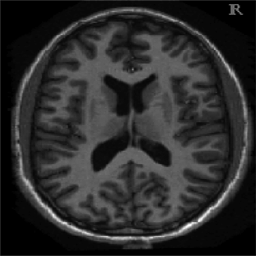

4.1. Uniform Gaussian noise

In this first experiment, we consider the denoising problem with brain scan images. The first set consists of images of pixels and Gaussian noise with zero mean and variance . The original and noisy images are shown in Figure 4.1. The domain decomposition-semismooth Newton algorithms run with the parameter values , , and . The results are shown in Figure 4.2. From the surface representation of , we can observe that is continuous and its shape is related to the one of the original image. In particular, the regularization is stronger in homogeneous regions in the image, and weaker where the image intensity undergoes variations on a smaller scale.